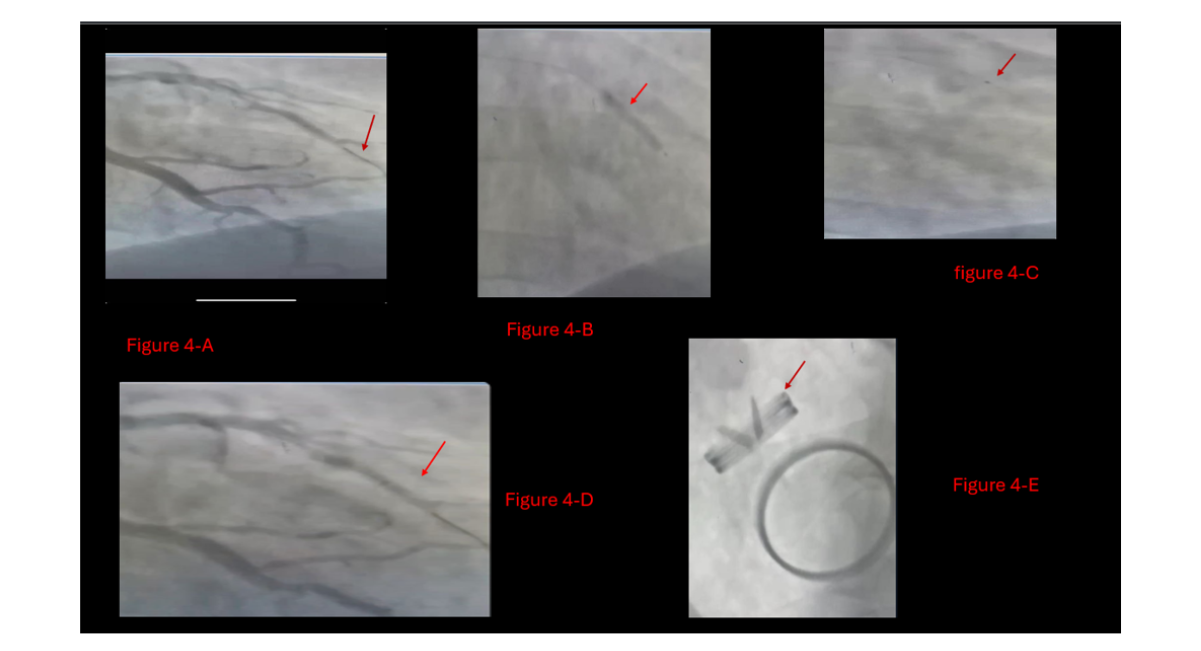

Following thrombolytic therapy, the patient's vital signs stabilized. Multiple runs of aspiration thrombectomy were performed. The patient’s hemodynamic status improved significantly, and he was transferred from the catheterization lab in stable condition, without stenting according to the deferred stent strategy (Figure 4).

Figure 4: Patient`s LAD during catheterization,

A: Wire in LAD crosses the thrombotic lesion and after full dose of metalase,

B: LAD balloon dilation,

C: Aspiration catheterization,

D: After balloon dilation and multiple runs of aspiration catheterization, LAD is partially opened with TIMI flow II,

E: Aortic valve functioning well at the end of the intervention in the first day.